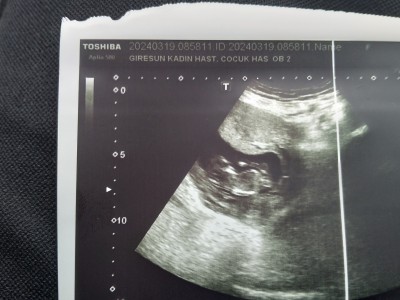

Ultrason fotoğrafı koyayım bak neymiş :D

image